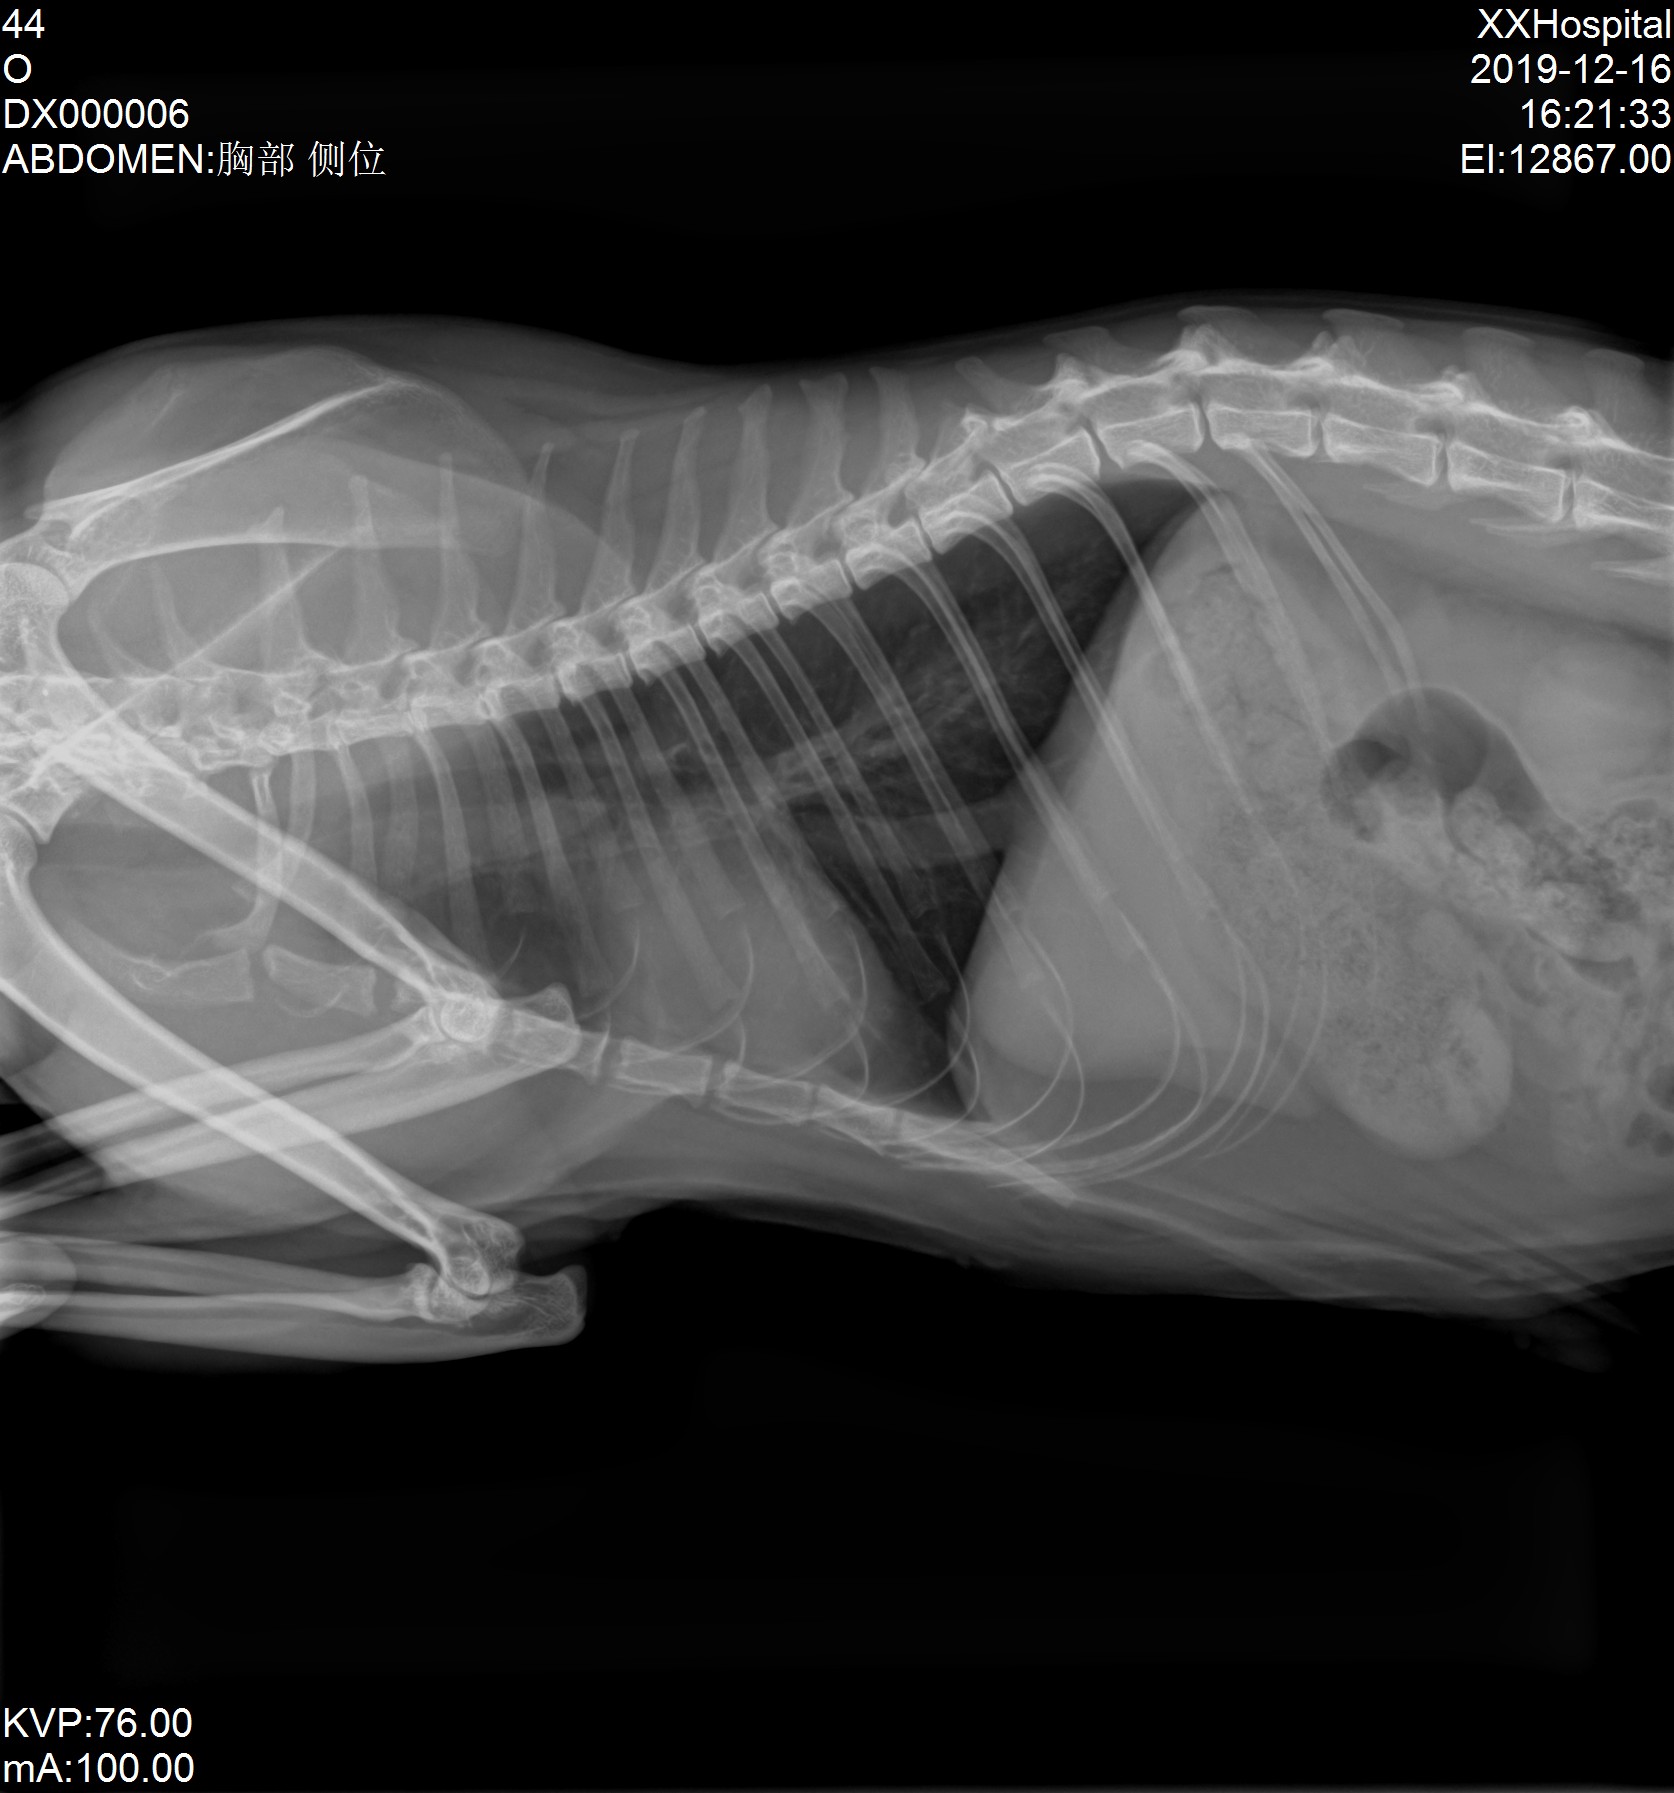

Share some clinical x-ray images by our veterinary DR system YSX056-PL with flat panel detector YSFPD-V1717X VET.

Here we'd like to share some clinical x-ray images by our veterinary DR system YSX056-PL with flat panel detector YSFPD-V1717X VET.